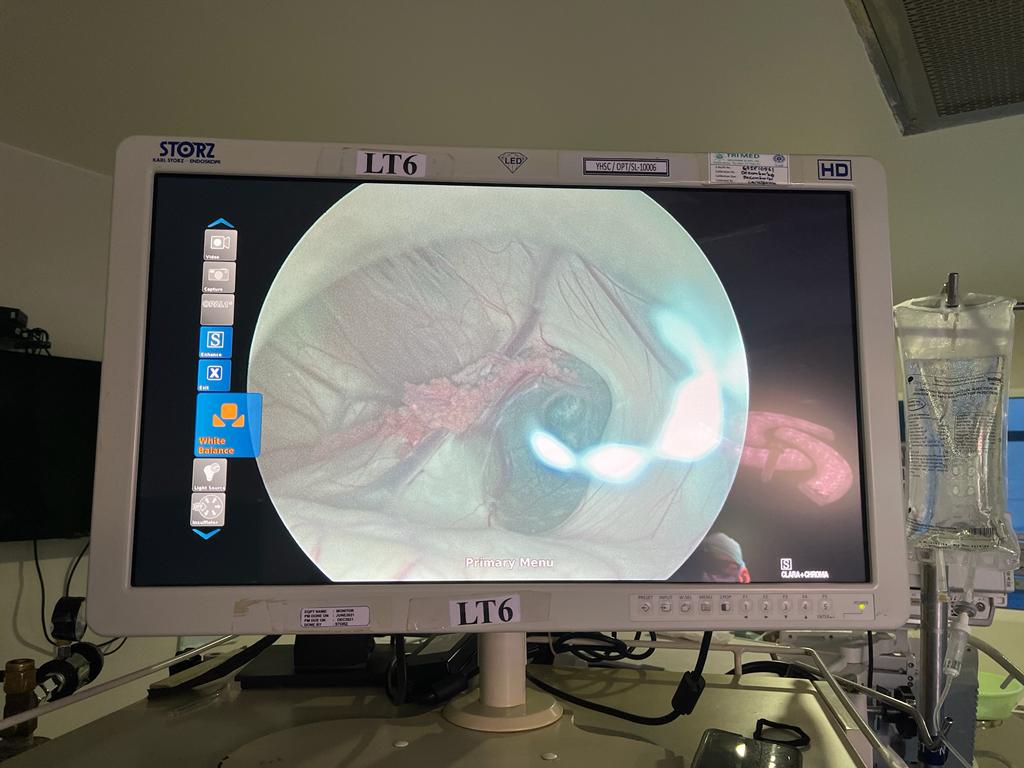

A laparoscope looks like a hysteroscope, but it is inserted into the pelvic and abdominal cavities to diagnose and treat gynecologic disorders.